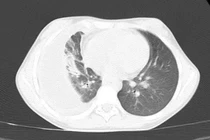

Trẻ 10 tuổi mắc bệnh viêm màng mủ phổi nguy hiểm

Viêm màng mủ phổi là tình trạng nhiễm trùng nặng, có nguy cơ dẫn đến nhiễm trùng huyết với tỷ lệ tử vong cao, vào khoảng 15% đến 20%.